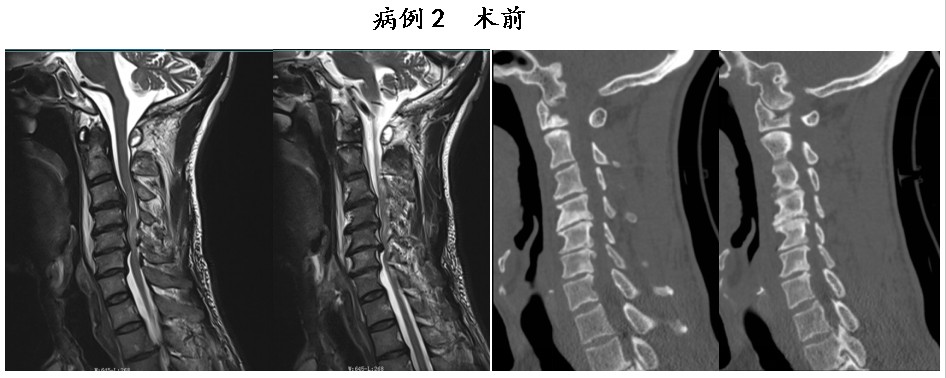

通訊員鐘嵐報道:近期,衡陽市中心醫(yī)院駐祁東縣人民醫(yī)院脊柱外科副主任醫(yī)師申寬宏團隊再創(chuàng)診療佳績,成功為2名頸脊髓損傷患者實施內(nèi)鏡輔助下頸椎前路減壓融合內(nèi)固定術(shù),實現(xiàn)術(shù)中脊髓零侵襲,術(shù)后患者神經(jīng)功能恢復(fù)良好、疼痛癥狀顯著緩解,贏得患者及家屬的高度認可,在區(qū)域內(nèi)樹立了良好的醫(yī)療口碑,取得了顯著的社會效益。

接診后,申寬宏團隊在高清視野下高效完成椎間盤或髓核摘除、椎管精準(zhǔn)減壓等核心操作,徹底解除脊髓與神經(jīng)的壓迫癥狀;同時,精準(zhǔn)植入融合器與內(nèi)固定裝置,實現(xiàn)病變椎體的牢固穩(wěn)定與骨性融合,有效重建脊柱正常生理曲度與力學(xué)平衡。

申寬宏介紹,該術(shù)式相較傳統(tǒng)開放手術(shù),具有創(chuàng)傷小、出血少、術(shù)后疼痛輕、恢復(fù)快等顯著優(yōu)勢,在保障治療效果的同時,大幅縮短了患者的住院時間,降低了術(shù)后并發(fā)癥發(fā)生風(fēng)險,為頸脊髓損傷患者的快速康復(fù)奠定了堅實基礎(chǔ)。